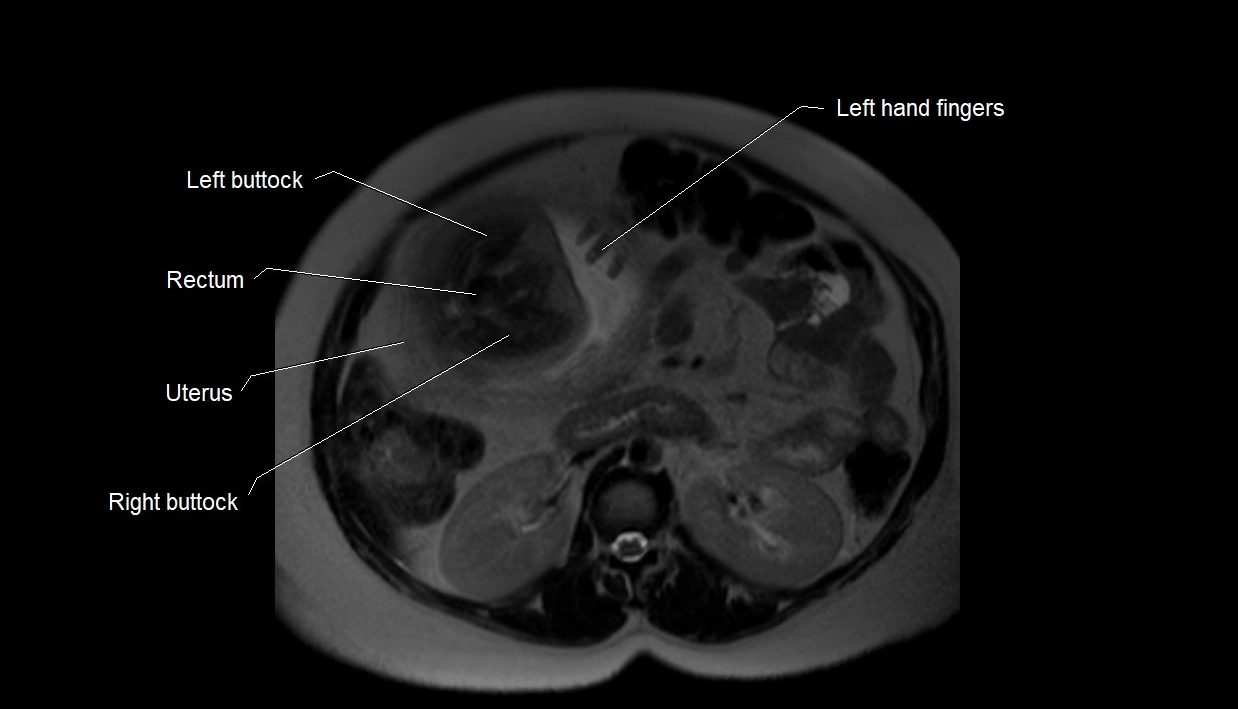

MRI Appearance

T2 HASTE (T2 GRE):

• Amniotic fluid shows very bright hyperintense signal

• Provides natural contrast against fetus and placenta

• Small particles (vernix) may appear as scattered hypointense foci within bright fluid

T1 GRE:

• Amniotic fluid shows low signal intensity (dark)

• Hemorrhage, infection, or proteinaceous content may cause focal or diffuse high signal intensity

MRI image

image